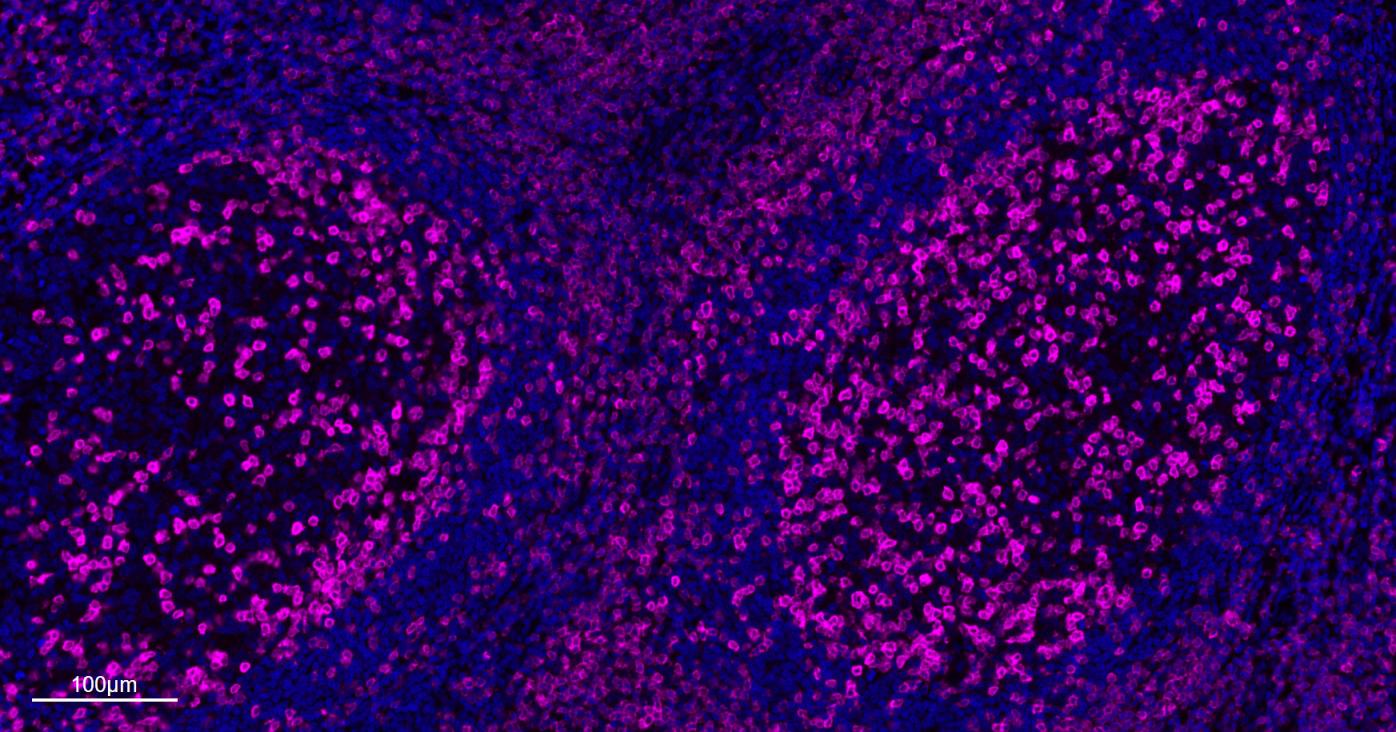

Paraformaldehyde-fixed, paraffin embedded Human Tonsil; Antigen retrieval by boiling in sodium citrate buffer (pH6.0) for 15 min; The section was incubated with CD3E Monoclonal Antibody, Unconjugated (bsm-60002R) at 1:200 overnight at 4°C. Followed by conjugated Goat Anti-Rabbit IgG antibody (Rose pink, bs-0295G-BF647), DAPI (blue, C02-04002) was used to stain the cell nuclei.